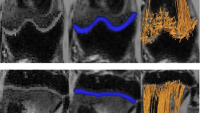

Led by Ola Kvist, the Kvist Lab is dedicated to advancing pediatric radiology through innovative research. Our focus lies in understanding the growth and development of young patients, with a particular emphasis on skeletal health and imaging techniques. We utilize state-of-the-art technology to investigate bone growth patterns, identify potential abnormalities, and explore the impact of various factors on skeletal development. Our research aims to improve diagnostic accuracy, optimize treatment plans, and ultimately enhance the quality of care for children.